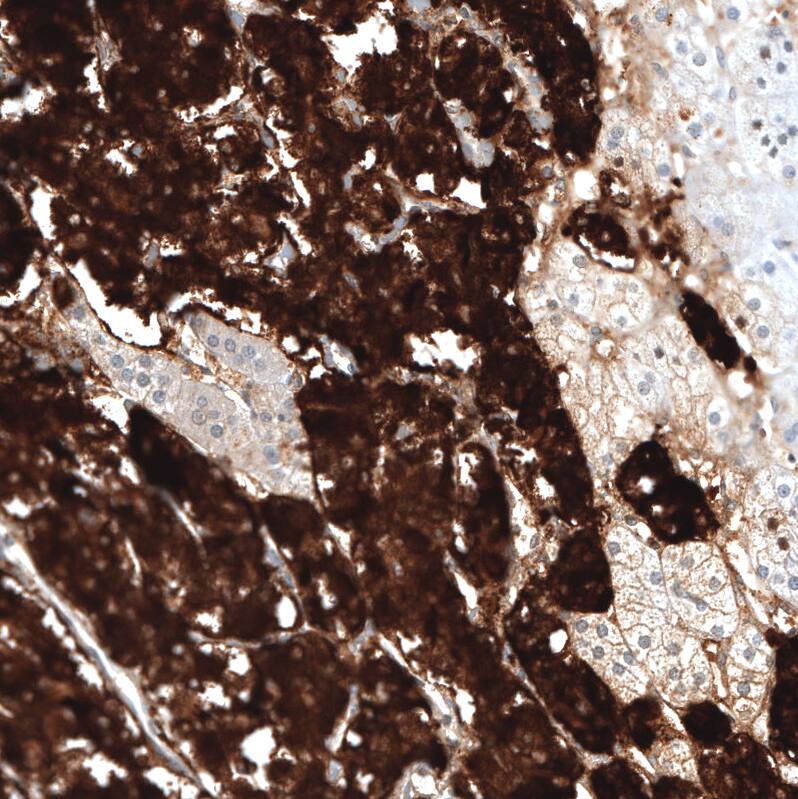

Staining of human adrenal gland shows strong cytoplasmic positivity in neuroendocrine cells.